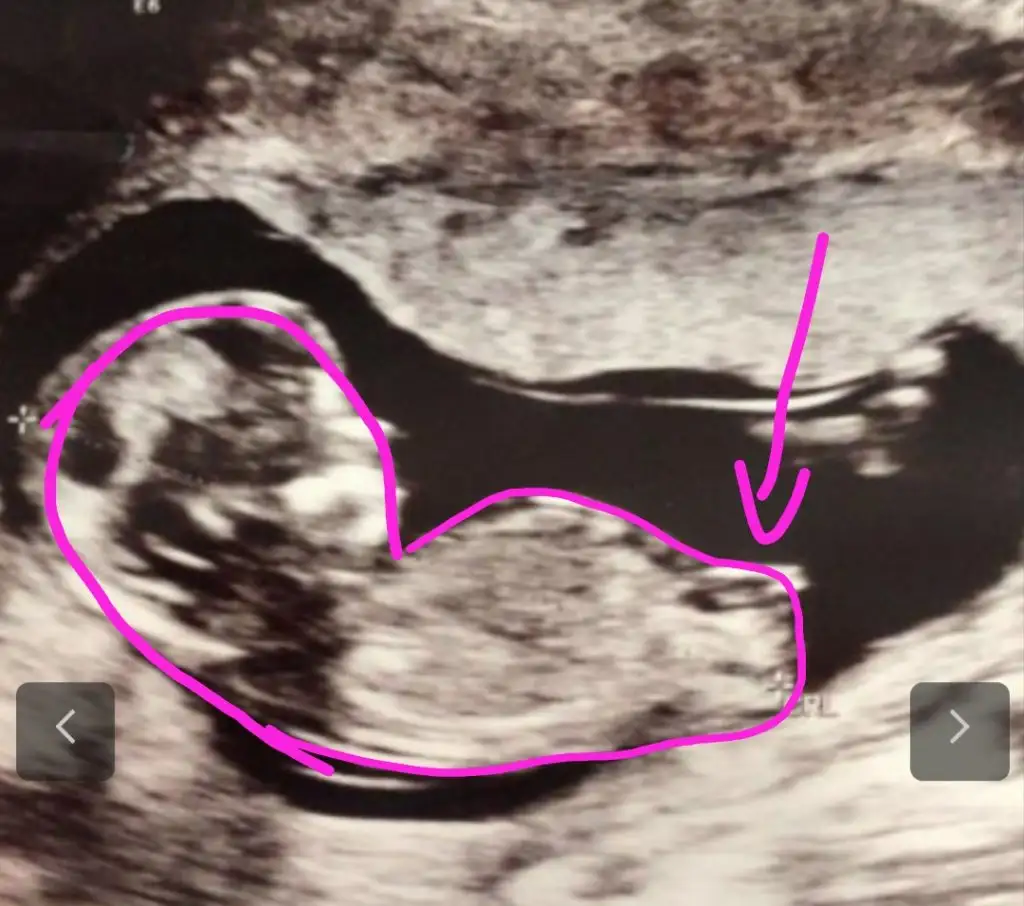

Net değil nubu emin olamadim başka USG varsa paylaşın sanki kız ama emin değilimMerhaba 12 haftalık tahmin edebilir misiniz![]()

Eki Görüntüle 2764653 doktor da Kıza benzetti. Çizebilir misiniz rica etsem. Teşekkürler.